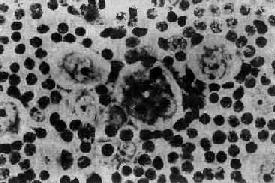

一、何杰金病何杰金病是恶性淋巴瘤的一个独特类型,与其他恶性淋巴瘤不同,具有以下特点:①病变往往从一个或一组淋巴结开始,逐渐由邻近的淋巴结向远处扩散。原发于淋巴结外淋巴组织者较少。②瘤组织成分多样,但都有一种独特的瘤巨细胞即Reed-Sternberg细胞。瘤组织内并常有多数各种炎症细胞浸润。 本病在欧美各国发病率较同,是青年人中最常见的恶性肿瘤之一。在我国发病率较低,大致占全部恶性淋巴瘤的10%~20%。 【病理变化】 病变主要发生于淋巴结,以颈部淋巴结和锁骨上淋巴结最为常见,其次为纵隔、腹膜后、主动脉旁等淋巴结。病变常从一个或一组淋巴结开始,很少开始即为多发性。晚期可侵犯血管,累及脾、肝、骨髓和消化道等处。 肉眼观察,病变的淋巴结肿大,早期无粘连,可活动。瘤组织浸润淋巴结包膜,并侵入邻近组织时则不易推动。相邻的淋巴结常相互粘连,形成结节状巨大肿块。切面灰白色呈鱼肉状,可见散在的黄色小坏死灶。 镜下,淋巴结的正常结构破坏消失,由瘤组织取代。瘤组织内的细胞成分多样,有些是肿瘤成分,有些是非肿瘤成分。瘤组织中有一种独特的多核瘤巨细胞,体积大,直径约15~45μm,椭圆形或不规则形;胞浆丰富,双色性或呈嗜酸性;核大,可为双核或多核,染色质常沿核膜聚集成堆,核膜厚。核内有一大的嗜酸性核仁,直径约3~4μm,周围有一透明晕。这种细胞称为Reed-Sternberg细胞(R-S细胞)。双核的R-S细胞的两核并列,都有大的嗜酸性核仁,形似镜中之影故称镜影细胞(图11-1)。这些双核和多核的R-S细胞是诊断HD的重要依据。

图11-1 何杰金病示镜影细胞 何杰金病的肿瘤成分中除典型的R-S细胞外,还有一些肿瘤细胞,形态与R-S细胞相似,但只有一个核,内有大形核仁,称为何杰金细胞。这种细胞可能是R-S细胞的变异型,不能作为诊断的依据。此外,还有一些变异的R-S细胞常见于本病的某些特殊类型:①有些细胞体积较大,胞浆淡染,核大,常扭曲,呈折叠状或分叶状;核膜薄,染色质细,核仁小,可有多个小核仁。这种细胞常见于淋巴细胞为主型何杰金病。②陷窝细胞(lacunar cell)多见于结节硬化型何杰金病。细胞体积大,胞浆丰富,染色淡或清亮透明,核大呈分叶状,常有多个小核仁。用福尔马林固定的组织,细胞浆收缩与周围细胞之间形成透明的空隙,好似细胞位于陷窝内故称陷窝细胞(图11-2)。③多形性或未分化型细胞,多见于淋巴细胞消减型何杰金病。细胞体积大,大小形态多不规则;核大,形状不规则,核膜厚,染色质粗,常有明显的大形核仁,核分裂像多见,并常有多极核分裂。